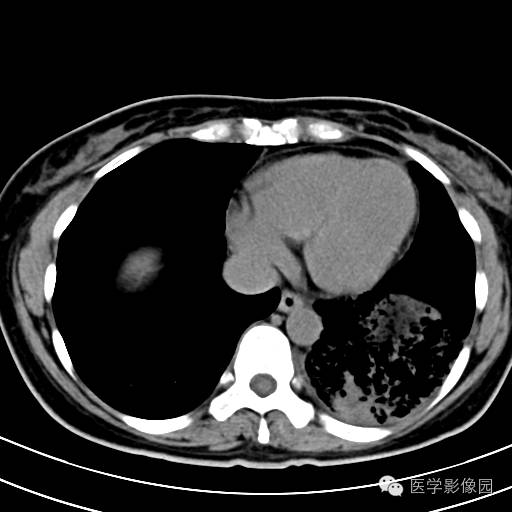

肺叶实变性支气管肺泡癌1例CT影像表现